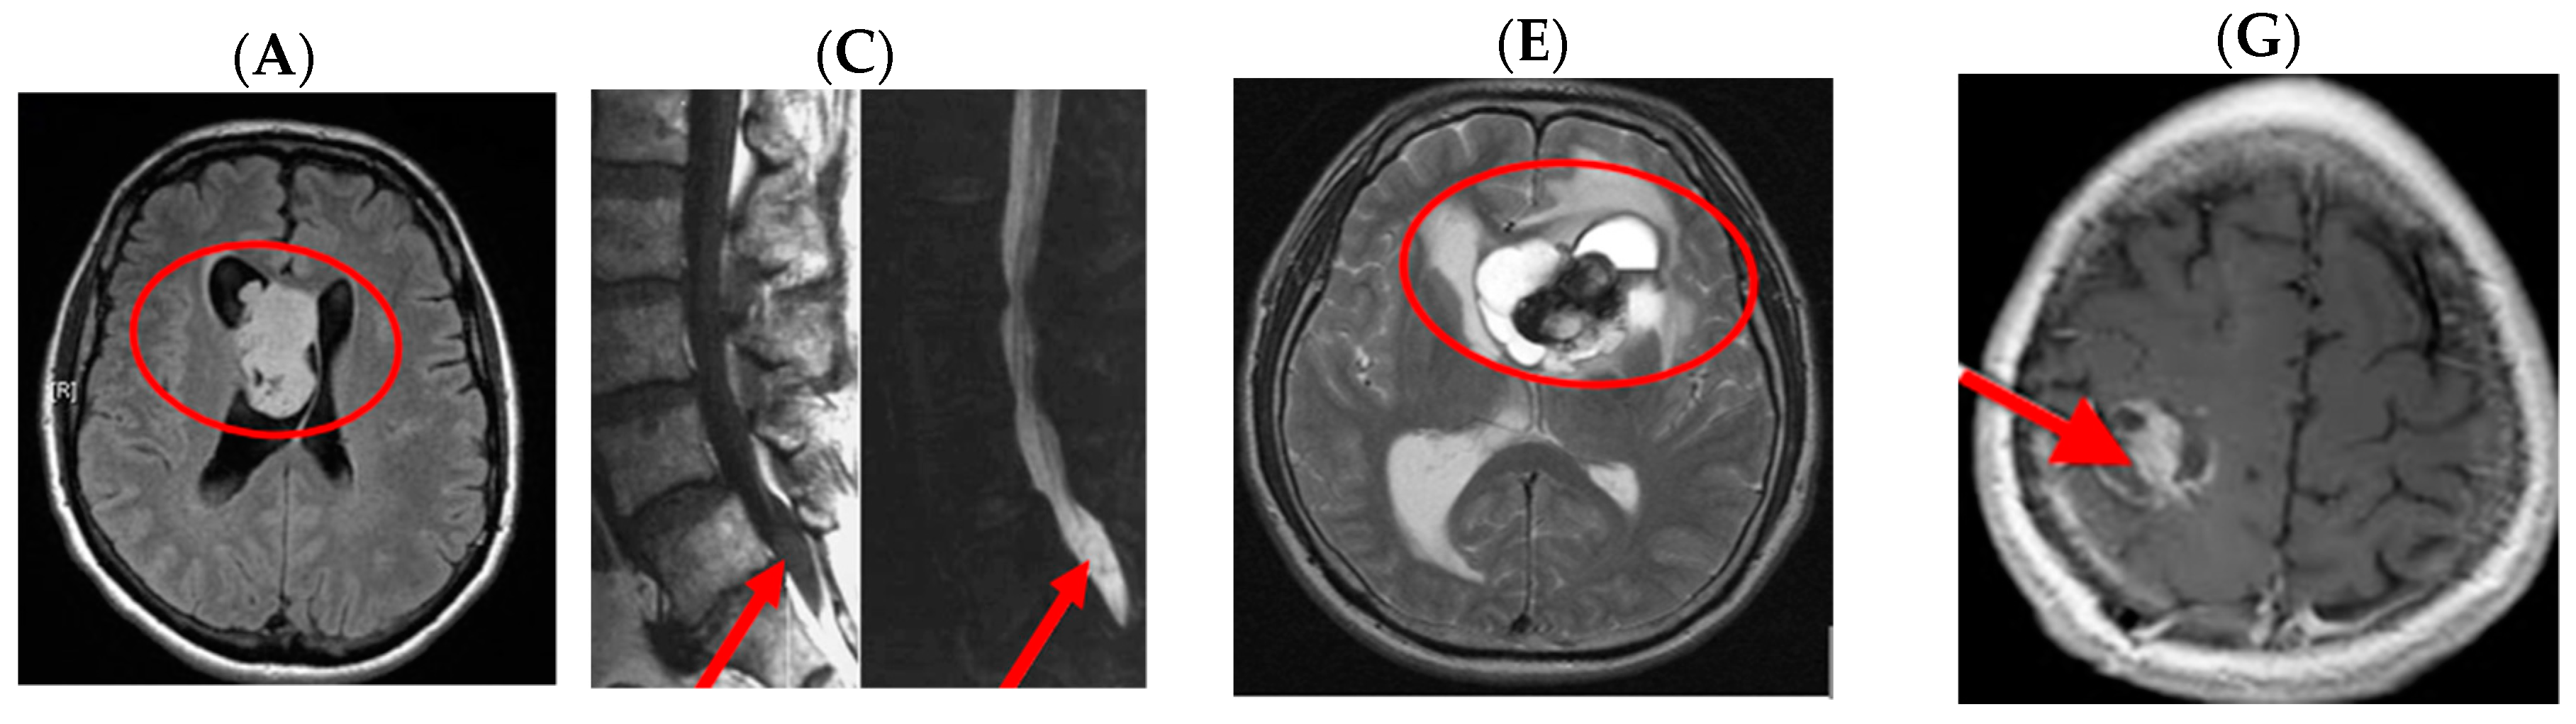

- Radiopedia; Jones, J.; Gaillard, F.; et al. Glioblastoma. Available online: https://radiopaedia.org/articles/glioblastoma (accessed on 27 March 2017).

- Wikipedia. Glioblastoma Multiforme. Available online: https://commons.wikimedia.org/wiki/File:Glioblastoma_(1).jpg (accessed on 18 July 2017).

- Wikipedia. Glioblastoma GFAP. Available online: https://commons.wikimedia.org/wiki/File:Glioblastoma_GFAP.jpg (accessed on 27 March 2017).

- Radiopaedia. Spine Ependymomas. Available online: https://radiopaedia.org/articles/spinal-ependymoma (accessed on 27 March 2017).

- Radiopaedia. Ependymoma. Available online: https://radiopaedia.org/cases/ependymoma-lateral-ventricle (accessed on 27 March 2017).

- CERN Foundation. Adult Ependymoma Images. Available online: http://www.cern-foundation.org/education/diagnosis/adult-ependymoma-images (accessed on 27 March 2017).